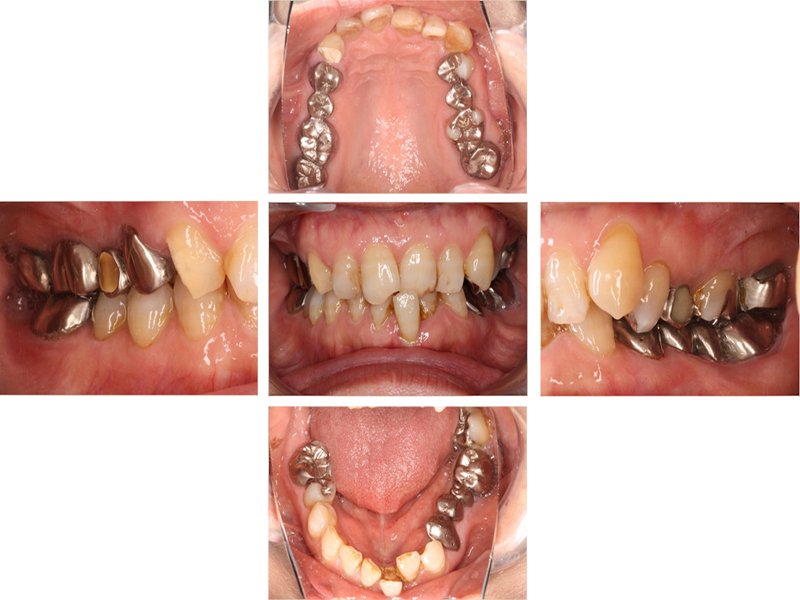

▼ ケース5 下顎前歯部叢生症例

初診時口腔内写真

初診時X線写真